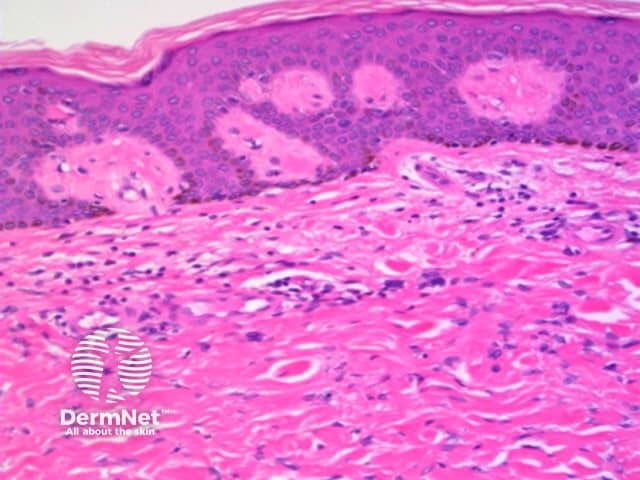

The histological features of lichen planus are:

Pathology of lichen planus